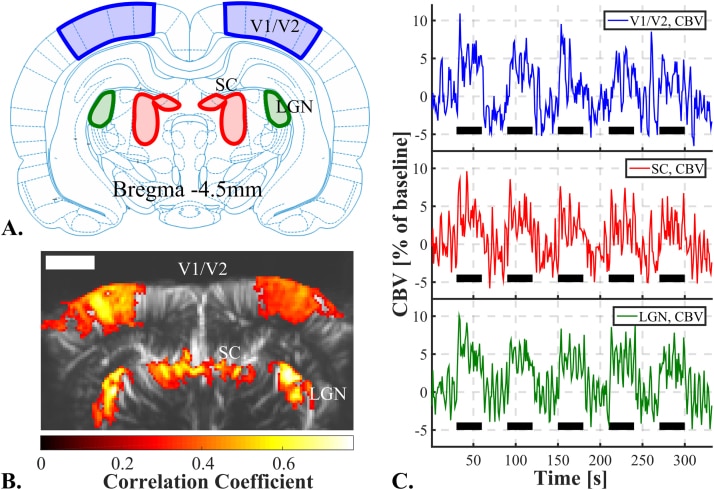

The high spatial resolution of fUS allows the creation of detailed retinotopic maps of animals performing complex visual tasks, as shown in a pioneering study of the rat (see the image below).

Nature Communications, 2019 (licensed under CC BY 4.0).